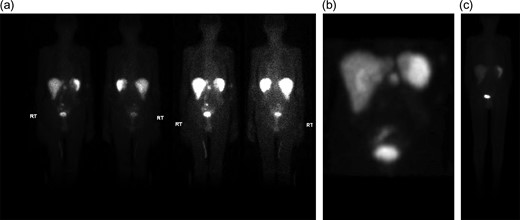

Initial inpatient evaluation started with pan endoscopy. Upper endoscopy demonstrated a Billroth II anastomosis with patent efferent and afferent limbs and no evidence of marginal ulceration or malignancy. Colonoscopy, likewise, was unremarkable. Radiographic evaluation with computed tomography of the abdomen and pelvis did not show evidence of pancreatic tumor or biliary ductal dilatation (Fig. 1). An octreotide scan, however, demonstrated increased activity near the head of the pancreas and abdominal aorta (Fig. 2 a-b). Endoscopic ultrasound did not fully evaluate the head of pancreas but showed no lesions in the left lobe of the liver, pancreatic body and tail. Capsule endoscopy then followed and was unremarkable. Despite being placed nil per Os, the patient’s diarrheal symptoms and hypokalemia persisted. Stool cultures obtained on admission demonstrated no growth.

(a–c) (a and b.) Octreotide scan demonstrating increased activity in the peripancreatic region (6.6 mCi of Indium-111 labeled octreotide). (c) Repeat octreotide scan (6 of Indium-111 labeled octreotide) at 4 months post-resection demonstrated normal distribution of activity in the liver, spleen and urinary system. No other focal area of activity was identified.

After exhaustive workup, the octreotide scan, as well as the classic constellation of clinical findings consistent with VIPoma, supported our decision to proceed with operative exploration with possible pancreaticoduodenectomy. Upon entry into the abdomen, no evidence of palpable or occult metastatic disease was found; however intraoperative ultrasound with color flow doppler localized two lesions less than one cm in size at the level of the uncinate process and ampulla. At this point, an open pancreaticoduodenectomy was offered to the patient’s family versus expectant follow up and they elected for a potentially curative resection given his ongoing symptoms. A pancreaticoduodenectomy was performed and modified to the patient’s existing Billroth II anatomy; afferent and efferent limbs were re-constructed to accommodate the new pancreatojejunostomy, gastrojejunostomy and choledochojejunstomy. At the conclusion of the case, a jejunostomy tube was also placed for enteral access. Following surgery, the patient had a prolonged post-operative course complicated by persistent diarrhea and was discharged post-operative Day 14 on supplementary enteral nutrition. At 2 two-month post-operative follow up, the patient had significant improvement of his diarrhea and had been weaned from enteral nutrition. A repeat octreotide scan 4 months following resection demonstrated radiographic resolution (Fig. 2b).